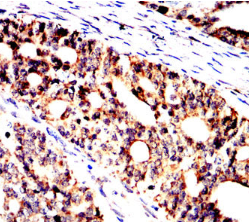

GMNN Mouse Monoclonal antibody[1H11G]

This gene encodes a protein that plays a critical role in cell cycle regulation. The encoded protein inhibits DNA replication by binding to DNA replication factor Cdt1, preventing the incorporation of minichromosome maintenance proteins into the pre-replication complex. The encoded protein is expressed during the S and G2 phases of the cell cycle and is degraded by the anaphase-promoting complex during the metaphase-anaphase transition. Increased expression of this gene may play a role in several malignancies including colon, rectal and breast cancer. Alternatively spliced transcript variants have been observed for this gene, and two pseudogenes of this gene are located on the short arm of chromosome 16.

Immunogen:    Purified recombinant fragment of human GMNN (AA: FULL 1-209) expressed in E. Coli.

IHC    1/200 - 1/1000